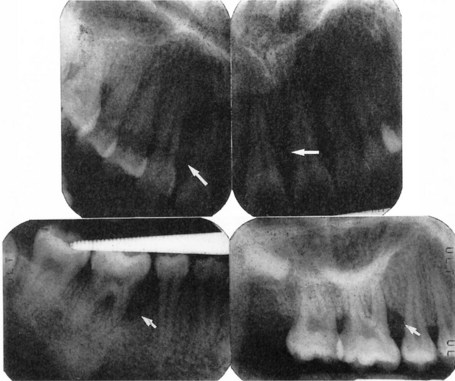

Clinical features

image

Fig. 33.5 Radiographic appearance of a patient with aggressive periodontitis showing localized periodontal bone loss (arrows).